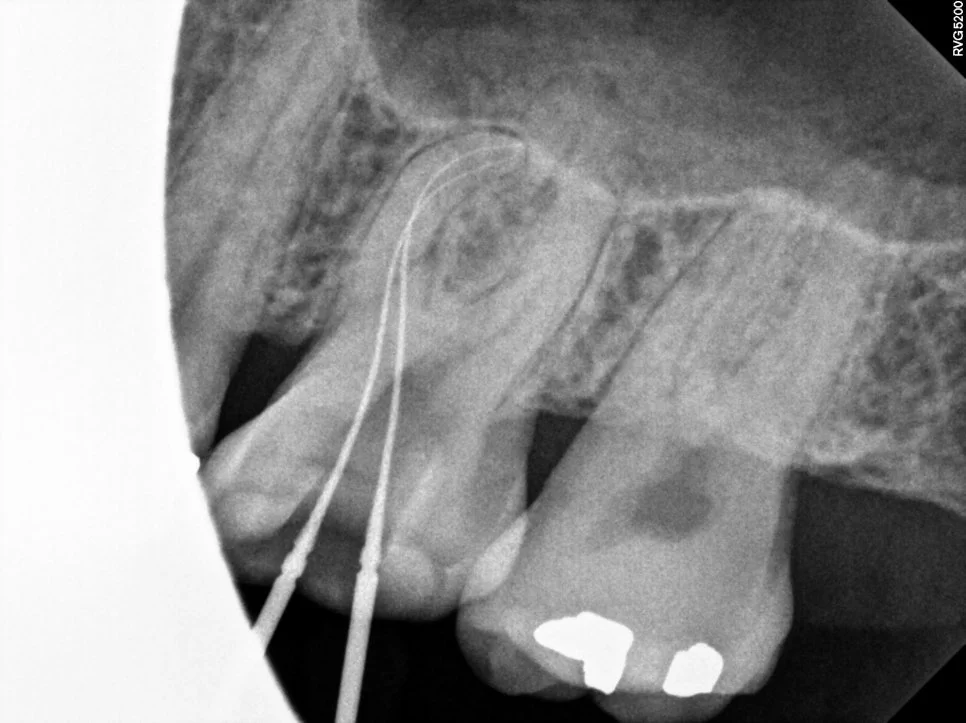

근관충전 결과

사진에 표기된 두 개의 신경관이 하나의 뿌리에서 각기 주행하는 다른 신경관입니다! 이렇듯 치아 내부의 신경관은 복잡하고 변이가 많아 신경치료를 모두가 어려워하는 실정입니다^^

신경치료가 완료된 후 촬영한 사진에서 모든 신경관이 가득 채워진 것 같으면 잘 된 신경치료로 볼 수 있습니다!